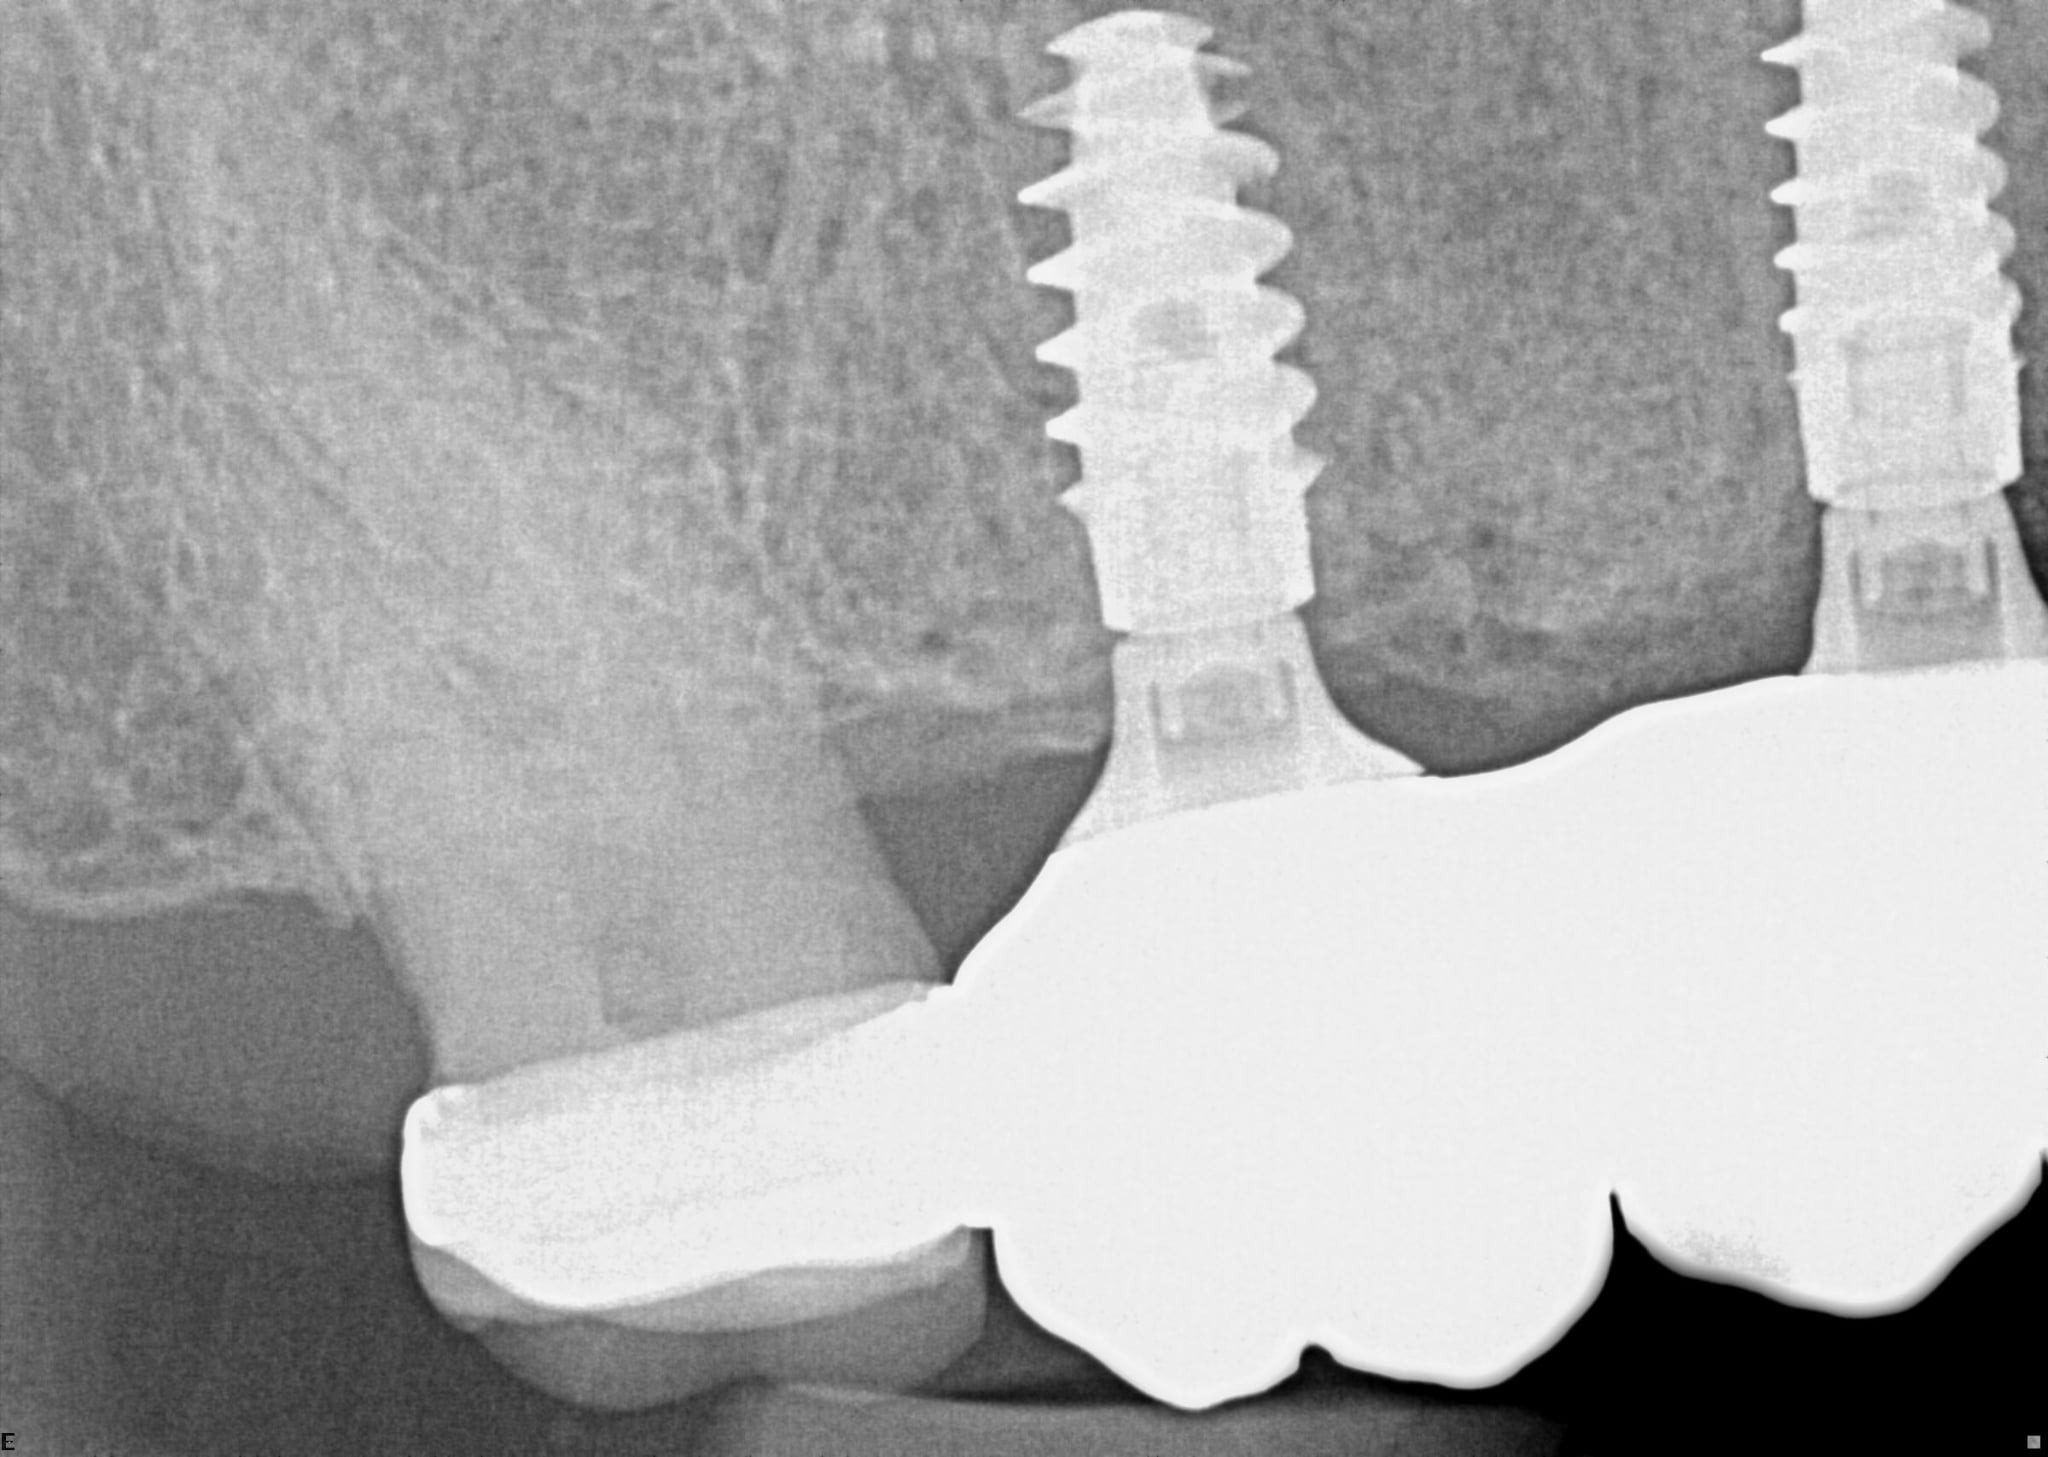

Which of the following is true regarding dental implant at site 2.6?

Which of the following is true regarding dental implant at site 3.6?